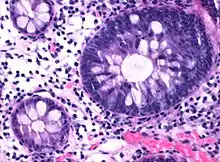

| Micrograph of hyperplastic polyp | |

Histopathologically, there are two main types of hyperplastic polyps, which have genetic differences, as well as different histologic structure, but no significant differences clinically.[4] The two main types of hyperplastic polyps are microvesicular mucin-rich type and goblet cell-rich type.[1] A mucin-poor type with eosinophilic cytoplasm, which is rare, was previously described.[4] However, the mucin poor type is no longer considered a distinct subtype.[1]

The luminal portion has a serrated ("saw tooth") appearance formed by tufts or folds of abundant apical cytoplasm. It contains glands with star-shaped lumina.[4] There are crypts that are elongated but straight, narrow and hyperchromatic at the base. All crypts reach to the muscularis mucosae.[4] The basement membrane is frequently thickened.[4]

Elongated, fat crypts and little to no serration. Therefore, they may not be obvious without comparing to adjacent normal intestinal wall.[4]

They are filled with goblet cells, extending to surface, which commonly has a tufted appearance.[4]